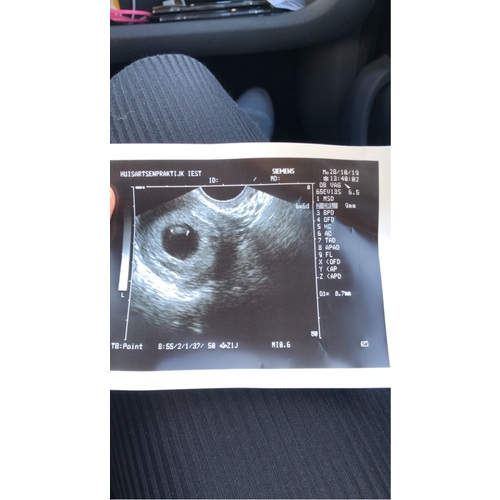

Dit was bij 6+6. We waren met 6+3 bij een andere echoscopist geweest en daar kregen we te horen dat er geen activiteit was en dat het mogelijk verkeerd zou gaan. Inmiddels 22+6 zwanger van een gezond meisje. Mocht je dus nog geen activiteit zien, wees dan niet meteen in paniek!